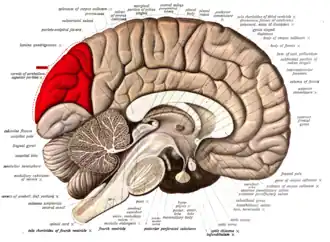

Medial surface of left cerebral hemisphere. (Cuneus visible at left in red.) | |

The cuneus (from Latin 'wedge'; pl.: cunei) is a smaller lobe in the occipital lobe of the brain. The cuneus is bounded anteriorly by the parieto-occipital sulcus and inferiorly by the calcarine sulcus.